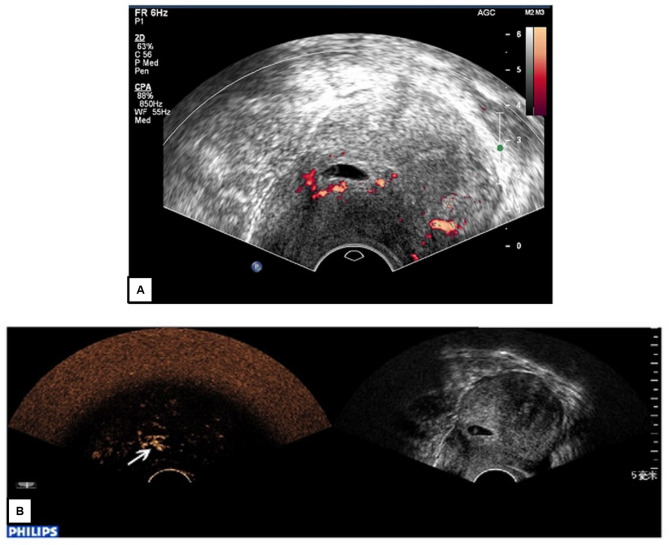

{"title":"Contrast-enhanced ultrasound for fetal and placental assessment: evidence, safety, and a roadmap for clinical translation.","authors":"Alushika Jain, Rajasbhala P Dhande, Pratapsingh H Parihar, Shivali Kashikar, Nishant Raj, Amit Toshniwal","doi":"10.1186/s13089-025-00449-x","DOIUrl":null,"url":null,"abstract":"<p><strong>Background: </strong>Fetal growth restriction (FGR), preeclampsia, and other placental disorders are leading contributors to perinatal morbidity and mortality, primarily due to impaired uteroplacental perfusion. Existing imaging modalities, such as Doppler ultrasound and fetal MRI, provide indirect or limited functional insights into placental and fetal perfusion, constraining timely clinical intervention.</p><p><strong>Objective: </strong>To evaluate contrast-enhanced ultrasound (CEUS) as a promising, safe, and real-time tool for assessing placental perfusion and its potential application in maternal-fetal medicine through comprehensive analysis of methodological parameters, safety profiles, and emerging computational techniques.</p><p><strong>Methods: </strong>A comprehensive synthesis of preclinical and clinical studies was conducted, focusing on the safety, efficacy, and current use of CEUS in pregnancy. Key findings were drawn from animal models (rats, sheep, macaques) and human studies involving 256 pregnant individuals, with detailed analysis of imaging protocols, contrast agent characteristics, and quantification methods.</p><p><strong>Results: </strong>CEUS utilizes intravascular microbubble contrast agents (1-8 μm diameter) that do not cross the placental barrier, enabling safe maternal imaging. However, size distribution analysis reveals sub-micron populations (8-20% by number) requiring careful evaluation. Preclinical models confirm CEUS ability to detect placental perfusion Changes with 54% reduction in perfusion index following uterine artery ligation (p < 0.001). Human studies demonstrate zero clinically significant adverse events among 256 cases, though critical gaps exist including absent biomarker monitoring and long-term follow-up. Emerging AI-enhanced analysis achieves 73-86% diagnostic accuracy using ensemble deep learning architectures. Current limitations include significant protocol heterogeneity (MI 0.05-0.19, frequency 2-9 MHz) and absence of standardization.</p><p><strong>Conclusion: </strong>CEUS presents a compelling solution for perfusion imaging in pregnancy, offering functional, bedside imaging without fetal exposure to contrast agents. However, methodological limitations, knowledge gaps regarding long-term outcomes, and the distinction between conventional microbubbles and emerging nanobubble formulations demand systematic research investment. Clinical translation requires standardized protocols, comprehensive safety monitoring including biomarker assessment, ethical oversight, and long-term outcome studies to support integration into routine obstetric care.</p>","PeriodicalId":36911,"journal":{"name":"Ultrasound Journal","volume":"17 1","pages":"43"},"PeriodicalIF":2.9000,"publicationDate":"2025-10-06","publicationTypes":"Journal Article","fieldsOfStudy":null,"isOpenAccess":false,"openAccessPdf":"https://www.ncbi.nlm.nih.gov/pmc/articles/PMC12501096/pdf/","citationCount":"0","resultStr":null,"platform":"Semanticscholar","paperid":null,"PeriodicalName":"Ultrasound Journal","FirstCategoryId":"1085","ListUrlMain":"https://doi.org/10.1186/s13089-025-00449-x","RegionNum":0,"RegionCategory":null,"ArticlePicture":[],"TitleCN":null,"AbstractTextCN":null,"PMCID":null,"EPubDate":"","PubModel":"","JCR":"Q2","JCRName":"Medicine","Score":null,"Total":0}

Results: CEUS utilizes intravascular microbubble contrast agents (1-8 μm diameter) that do not cross the placental barrier, enabling safe maternal imaging. However, size distribution analysis reveals sub-micron populations (8-20% by number) requiring careful evaluation. Preclinical models confirm CEUS ability to detect placental perfusion Changes with 54% reduction in perfusion index following uterine artery ligation (p < 0.001). Human studies demonstrate zero clinically significant adverse events among 256 cases, though critical gaps exist including absent biomarker monitoring and long-term follow-up. Emerging AI-enhanced analysis achieves 73-86% diagnostic accuracy using ensemble deep learning architectures. Current limitations include significant protocol heterogeneity (MI 0.05-0.19, frequency 2-9 MHz) and absence of standardization.